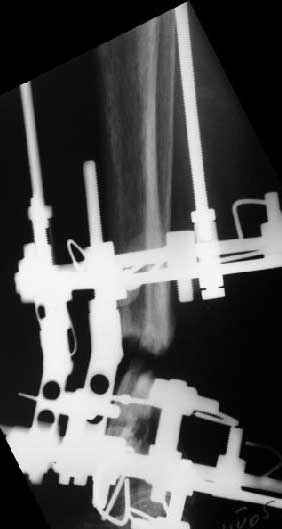

Аппарат - чтобы плавно исправить ось. В приложении - снимки на момент окончания коррекции в аппарате, фото с операции, и послеоперационная рентгенограмма.

Диаметр гвоздика 10,5 мм. Пришлось укорачивать до 23 см - уж очень миниатюрная дама, отверстия насверлил под 45 градусов, под 5 мм винты. По оси удалось сблизить до этого положения. Заперли гвоздь пока статически с планом через 2 месяца верхний винт убрать. Но это ей придется уже в Ташкенте сделать. Что скажете? Спасибо.

In attachment - x-rays at the end of alignment, the surgery, and result. The nail was cut to 23 cm. Four 45 degree holes were pre-drilled at the distal nail tip. The nail was locked statically

after some impaction. Dynamization is considered in 8 weeks. Any comments/critics?

Some wires were intentionally inserted to leave needed space for the nail, some were removed at the moment of nail insertion. I inserted one distal screw and then removed the frame, then inserted rest ones.